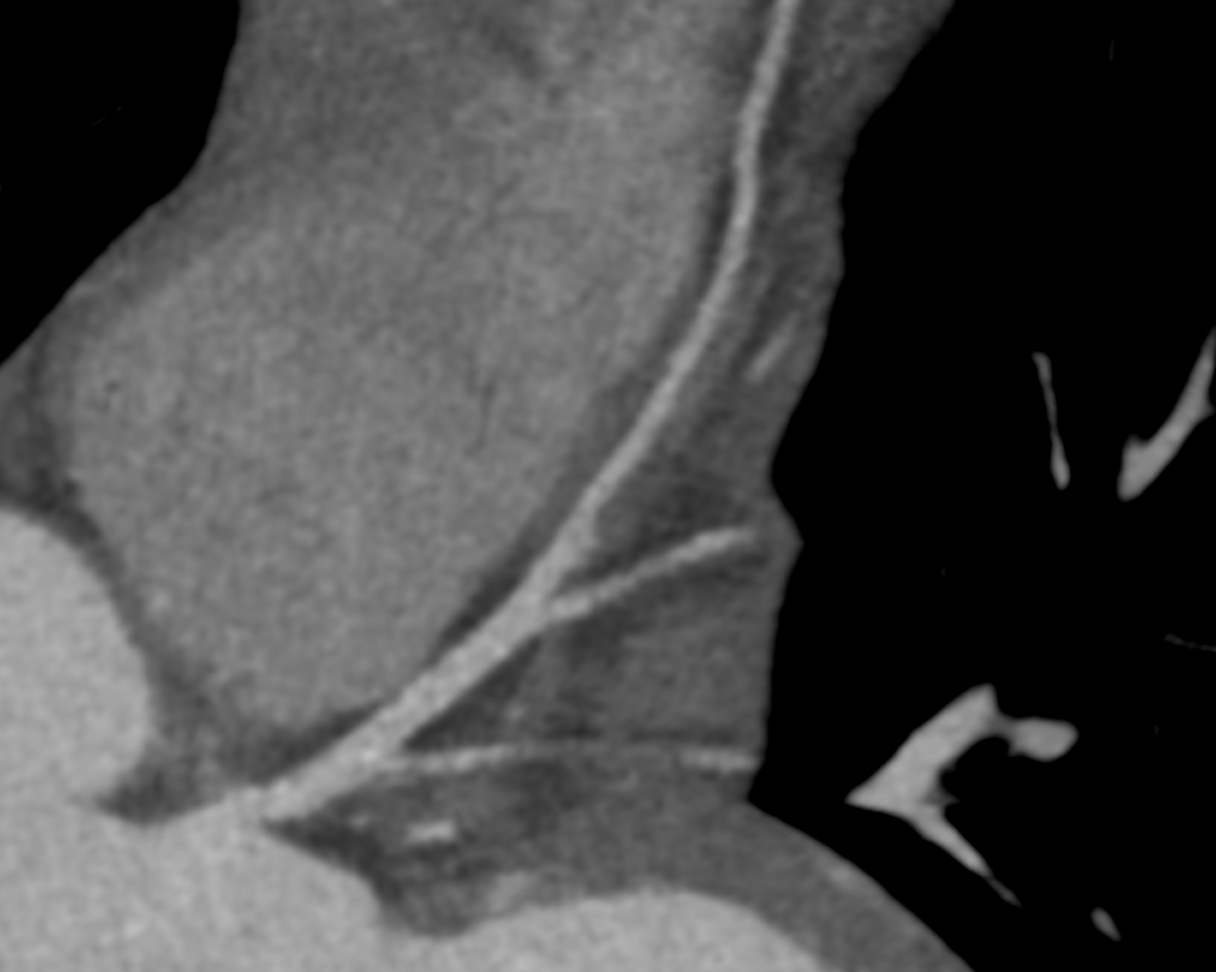

1-Beat Cardiac migliora la qualità diagnostica dell’angio-TC coronarica

L’angio-TC coronarica (CCTA) è uno strumento diagnostico essenziale per l’identificazione delle malattie coronariche, ma la sua affidabilità può essere compromessa nei pazienti con frequenza cardiaca elevata. Grazie ai progressi tecnologici, la modalità 1-Beat Cardiac consente ora di ottenere immagini di alta qualità anche in condizioni di elevata frequenza cardiaca.